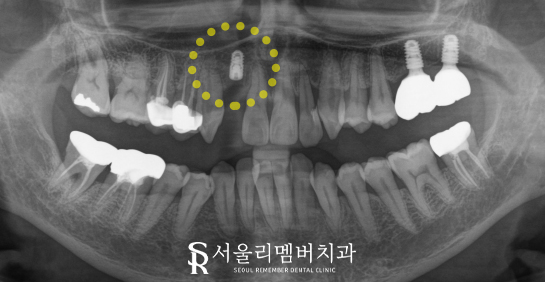

엑스레이 검사를 통해 자세히 확인한 결과,

해당 치아는 이미 이전에 신경치료

처리가 되어 있는 상태였는데요,

아쉽게도 뿌리 부위가 약해졌고

충치가 깊어져 자연치를 살리기에는

힘든 상태였습니다. 이런 경우,

재근관 제거술로는 해결이 어렵기에

발치를 고려해야 됩니다.